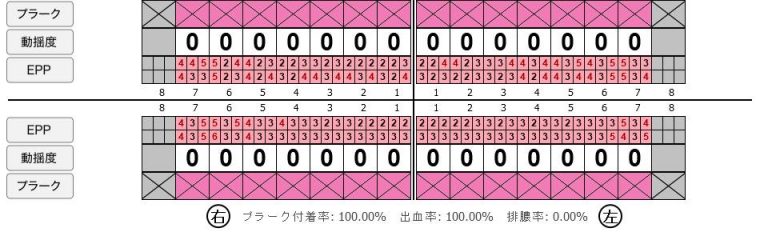

症例1

Before

after

Before

after

基本情報

| 年齢・性別 | 52歳・男性 |

|---|---|

| 主訴 | 主訴:久しぶりの歯医者なので歯石をとってほしい 治療部位:全顎 |

| 治療内容 | 1.歯磨き指導、歯肉縁上の歯石除去 2.歯磨きの確認、指導(磨けるようになるまで) 3.歯磨きの確認、指導、歯肉縁下の歯石除去(SRP) 4.PMTC 5.再評価、歯磨きの確認、指導 |

| 治療期間 | 1日 |

| 治療費 | 合計17,560円 ・内訳 1、歯周基本検査・歯磨き指導、縁上スケーリング:1,800円 2、歯周精密検査・SRP(スケーリング・ルートプレーニング)、歯磨き指導:2,130円 3、SRP、歯磨き指導:3回(1,530円×3回) 4、PMTC、全顎再スケーリング、歯磨き指導:5,500円(自費診療)+1,260円 5、再評価(歯周精密検査)、歯磨き指導:2,280円 ※PMTC以外、保険診療3割負担 (2023年5月現在現在) |

| リスク・副作用 | ・毎日の歯磨きが不十分だと歯石を除去しても再度歯石がついてしまう ・最初は歯磨きのときに出血してくることがあるが、細菌が減って歯茎が引き締まってくると徐々に出血は落ち着いてくるため痛みがなければ辛抱強く磨いてもらう ・歯周病は時間をかけて静かに進行する病気なので、歯周病を治すにはそれなりに期間がかかる、すぐには治らない ・歯ぐきが引き締まると歯茎が下がり歯間に隙間ができる可能性がある |

| 治療方針 | 一時的な治癒ではなく、将来的にこの治療が活かされるよう、患者さん自身である程度自己管理ができるようになることを目標とした |

| 特記事項 | ふつうのブラシと電動歯ブラシ使用(ブラウン丸型使) 歯間ブラシを1日1回は最低でも使って頂いた |

| 担当者所見 | あまり器用な方ではなかったため、決まったところがいつも磨けず奥歯に歯間ブラシがなかなか入れられませんでしたが、歯間ブラシのサイズを変えてみたり、内側から入れてみたりと試行錯誤してなんとかある程度磨けるようになりました。 その結果、出血が100%から7%へ激減することができました。 ただSRPをしただけではここまでの結果は出なかったと思います。 それほど日々のセルフケアが重要だということを再認識しました。 歯周ポケットが残っている部位、出血がある部位に関しては引き続き歯磨きを念入りに行なってもらう。 |